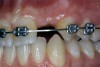

Before the day of surgery, the patient was seen by the orthodontist for the removal of the orthodontic brackets. The patient still was not pleased with the position of the two centrals, and it was determined that this would be addressed after implant placement (Figure 13A). The anatomical variations of the crestal tissue and lack of interdental papilla can be appreciated in the close-up views of the right and left sites (Figure 13B and 13C). There were no surprises on the day of surgery as all of the decisions were made during the planning phase, before the scalpel ever touched the patient. The occlusal view of the CT 3D model revealed the wider alveolar ridge on the right side and thinner crest on the left side (Figure 14A). This was confirmed when the full thickness mucoperiosteal flaps were elevated, and the underyling bone revealed (Figure 14B). The tooth-borne templates were designed to facilitate the drills and drilling sequence specific to the diameters of the predetermined implants (Figure 15A). Each template contained an embedded 5-mm long stainless steel tube, which was approximately 0.2-mm wider than each drill (just wide enough to allow for the drills to rotate freely). Once positioned over the natural teeth, the template was secure and offered precision accuracy in transferring the implant locations from the original software-designed plan, allowing the potential for internal and external irrigation (Figure 15B). The 3.7-mm diameter Tapered Screw-Vent implant drilling sequence requires three drills: pilot, intermediate, and final sizing. Thus, three separate templates were fabricated to a.commodate these sizes. The templates were removed easily and replaced with the next sequential size in less time than it takes to change the drill on the surgical handpiece. After the osteotomies had been.completed, the implants were delivered to the site (Figure 16A and Figure 16B). For this internal hex connection implant, the author r.commends that the flat of the antirotational hex be positioned to the facial for proper orientation of the restorative.components (Figure 17A). Preprepared margins were created from a milled titanium fixture mount transfer post, which was delivered to the implant as support for an immediate transitional restoration. The facial “dot” helped confirm the orientation of the abutment to the facially positioned flat side of the internal hex connection (Figure 17B). Before cementation of the transitional acrylic restorations, a closed-tray, fixture-level impression was made, and a soft-tissue model fabricated.

Figure 13a  Before implant surgery, the orthodontic brackets were removed, revealing (A) the position of the centrals, and (B, C) the anatomical variations of the crestal tissue and lack of interdental papilla.

Figure 13a

Figure 13b  Before implant surgery, the orthodontic brackets were removed, revealing (A) the position of the centrals, and (B, C) the anatomical variations of the crestal tissue and lack of interdental papilla.

Figure 13b

Figure 13c  Before implant surgery, the orthodontic brackets were removed, revealing (A) the position of the centrals, and (B, C) the anatomical variations of the crestal tissue and lack of interdental papilla.

Figure 13c